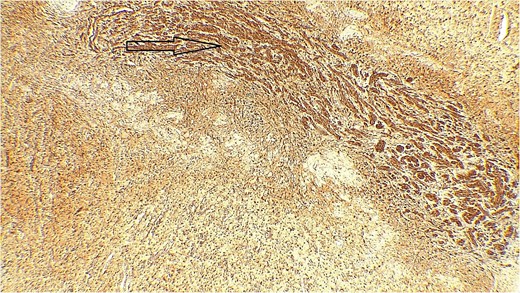

The result of the fine needle aspiration (FNAC) was a bland-looking spindle cell lesion, suggestive of a neural origin lesion like schwannoma. The patient was positioned in a supine position after she received general anesthesia. The face was turned to the opposite side of the tumor with a slight extension of the neck. An S-shaped incision was carried out in the front of the ear to the ear lobule, then it curved around the mastoid process posteriorly near the mastoid process and swung to the upper cervical creases smoothly. The cervical-facial skin flap was elevated with dissection to expose the tumor adequately, and then a traction suture was placed over the earlobe to widen the visual field for the operator. Dissection was carried out until the tumor was completely exposed, showing a smooth, ovoid, and whitish mass along the main trunk of the facial nerve (Fig. 1). The nerve was seen entering and exiting the posterior aspect of the mass on both sides. The layers over the mass were opened, and the mass was enucleated, leaving a flattened nerve posteriorly. No parotid gland excision was carried out. The postoperative histopathological examination revealed neurofibroma (Fig. 2) with a positive expression for S100 immune stain (Fig. 3). Postoperatively, the patient developed moderate (grade III) facial nerve dysfunction with obvious but not disfiguring deformity of the right side of the face, likely due to the pressure effect of the mass or traction during the operation. Two months after the operation, the facial nerve status improved to grade one, and after 4 months, she developed full recovery of facial nerve function.

Immune stain S100, strong nuclear and cytoplasmic staining pattern in the tumor cells.